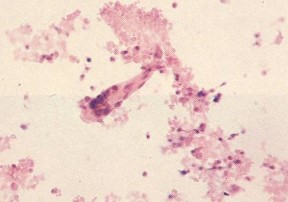

consolidation in the right lower or middle lobe (left image). A microscopic view

of the patient's pleural fluid shows a classic "comet cell" - a comet-shaped fusion

of epithelial cells - as well as leukocytes and cellular debris. The effusion also

contains high levels of rheumatoid factor and immune complexes, and a characteristically

low pH and glucose level (right image).